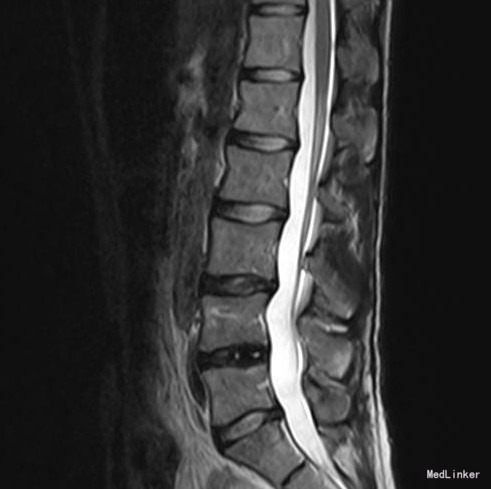

椎管侧隐窝占位1例

左侧下肢放射痛1月加重2天

腰椎前屈受限,腰4-5左侧棘突旁压痛,左侧直腿抬高试验小于30°,肌力正常。

腰椎椎管内占位 腰椎后路开窗减压+椎间融合+内固定术